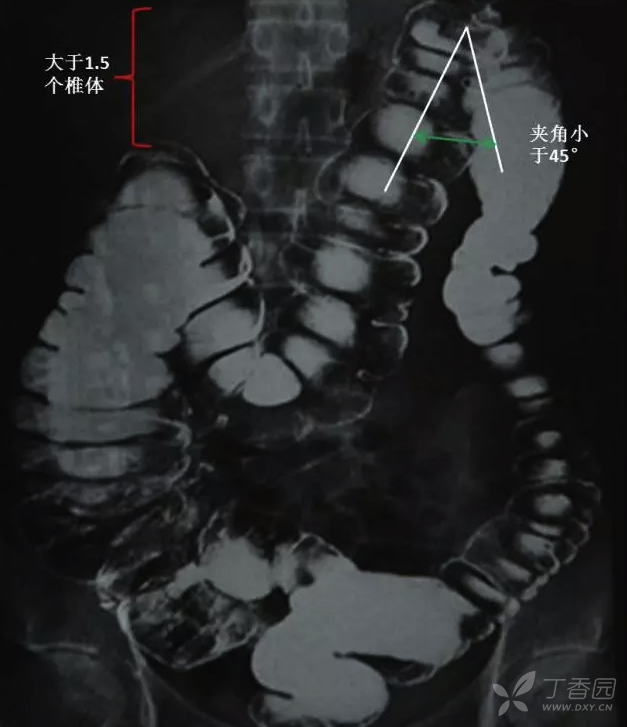

丁香园论坛

图片尺寸627x727